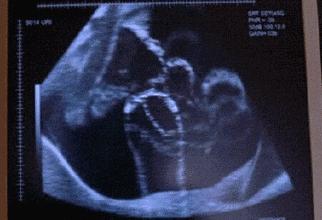

胎动,顾名思义指的就是胎宝在子宫里的活动,但这不单单是胎宝生命的象征,更是孕妈第一次真正感受到胎宝存在的象征。

在整个孕期中,胎动并不是一直不变的,在各个阶段胎动的情况是不一样的,所以也存在胎动变少的情况。就算胎动变少了,只要胎动依然有规律,有节奏,起伏变化不突兀,就没有多大问题。

到了孕晚期,由于胎儿慢慢长大,胎儿在子宫内的活动范围相对变小,此时的胎动幅度会减弱,所以此时胎动变少了是无需过分担心的。而且不是所有胎儿都喜欢动的,有些宝宝天生较安静,不喜欢乱动而已。如果妈妈一直比较忙碌,没有安静下来,当然就不能一直感受到胎儿的动静,自然就觉得胎动变少了。